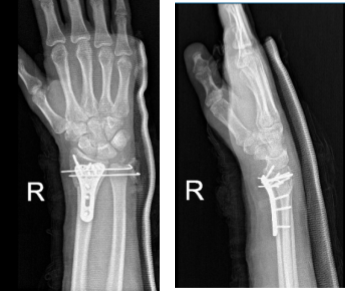

After one-week post-operative the patient was advised to return with X Ray results. Result was presented and discussed the surgically treated fracture of the right wrist. He is doing well and will continue the long arm splint.

Right wrist X-ray 3 or more views-1st week post operative